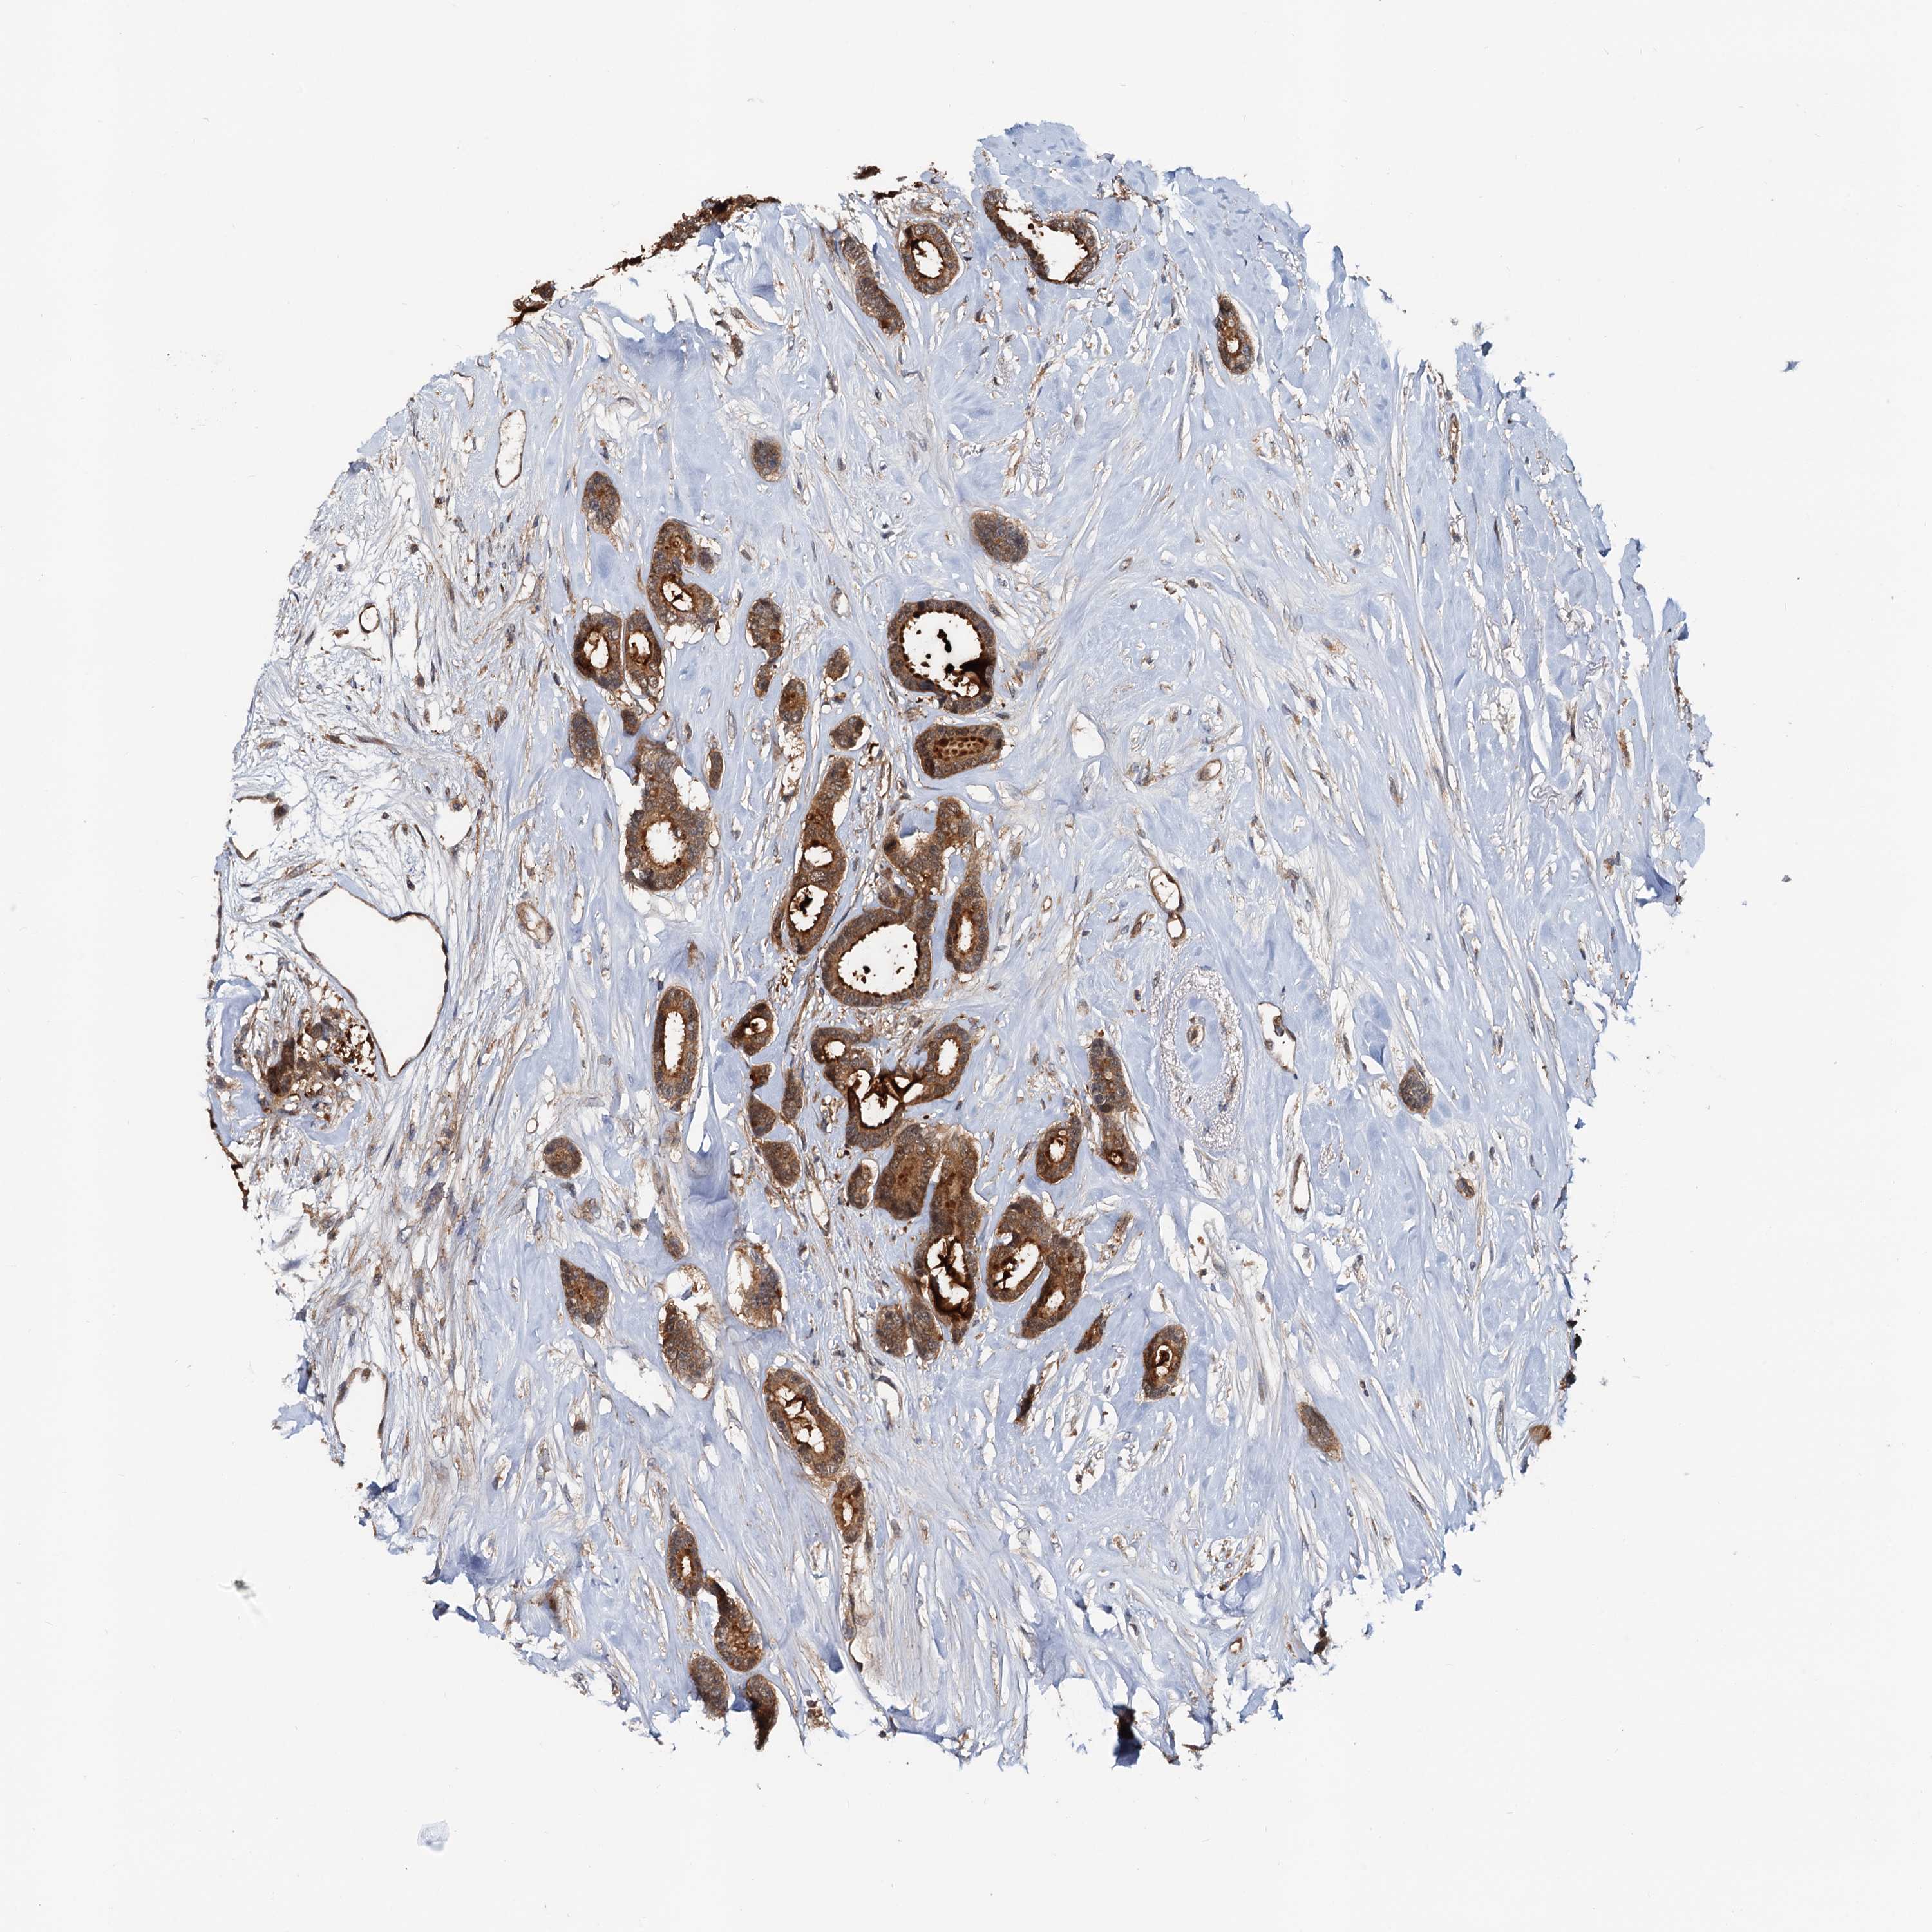

CANCER BREAST CANCER Show tissue menu

BRCA TCGA BRCA VALIDATION PROTEIN EXPRESSION